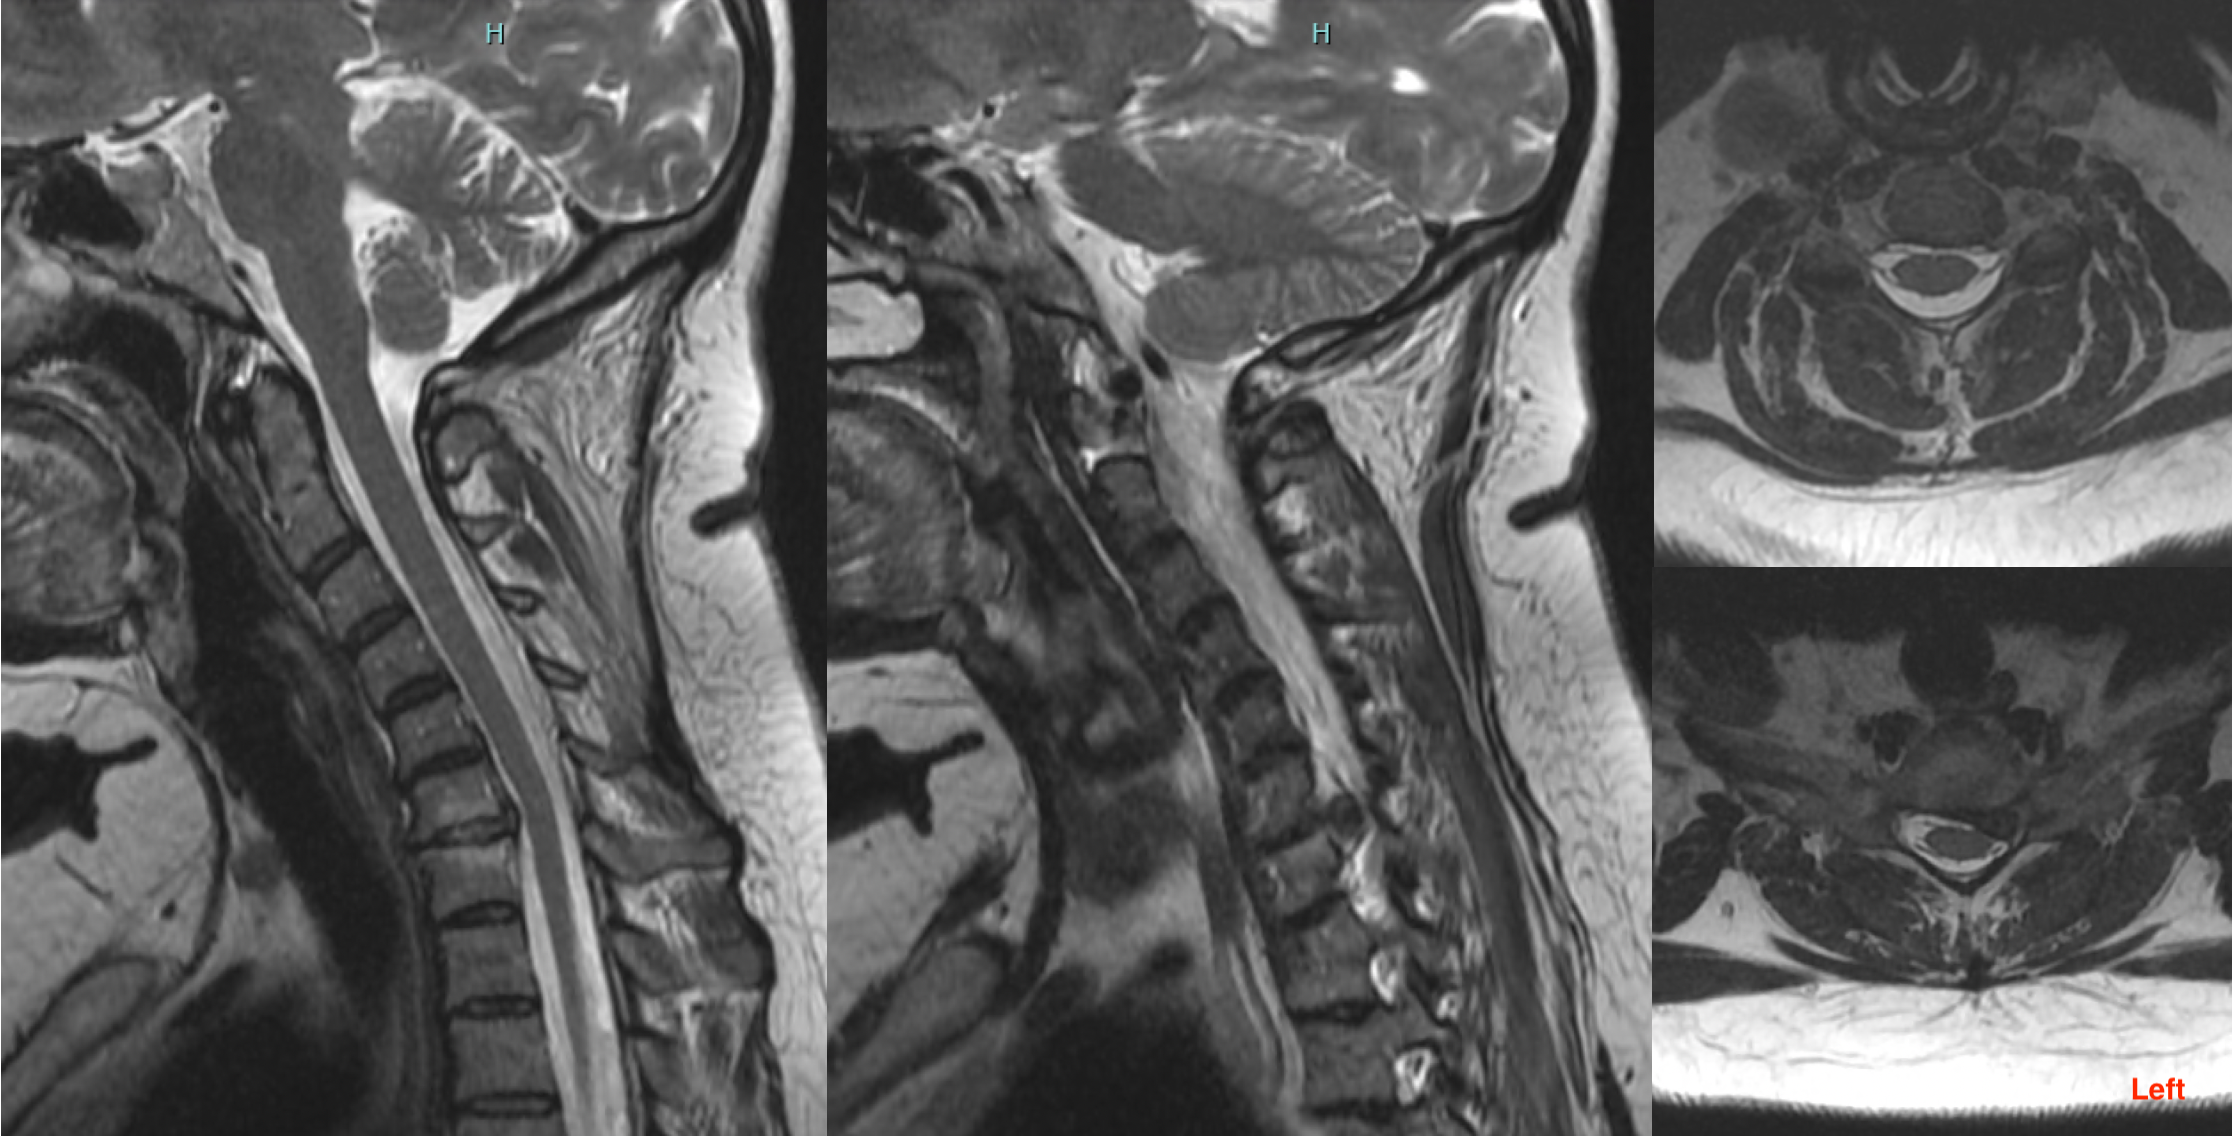

Diagnosis and Investigations

The diagnosis of cervical radiculopathy and myelopathy is usually made clinically based on history and examination. It is then confirmed with radiological imaging tests most notably an MRI scan. Other imaging tests, such as X-ray and CT are sometimes appropriate. Occasionally, electromyography (EMG) or nerve conduction study (NCS) are required.